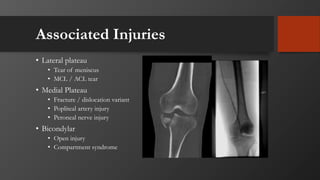

Associated Injuries

• Lateral plateau

• Tear of meniscus

• MCL / ACL tear

• Medial Plateau

• Fracture / dislocation variant

• Popliteal artery injury

• Peroneal nerve injury

• Bicondylar

• Open injury

• Compartment syndrome